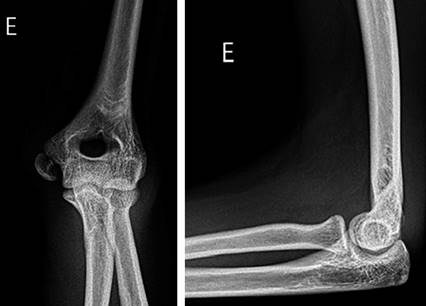

Figura 9: Radiografía en proyección anteroposterior y lateral de una paciente de 15 años con fractura del epicóndilo medial.

Figura 10: Radiografía en proyección anteroposterior y lateral, dos años después de la cirugía de fractura del epicóndilo medial del húmero fijada con la técnica «Inside-out».